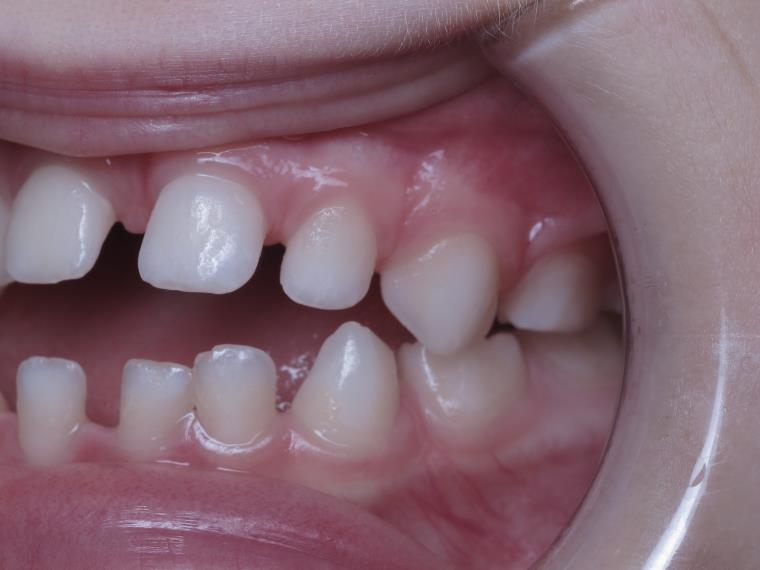

18 béance inversé droit 4 ans

inversion des dents postérieur et espace entre l'arcade du haut et du bas (béance)

sectionnel multibagues pendant 8 mois

bilan de début et en cours de traitement